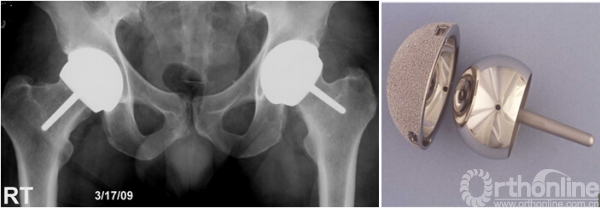

我使用CONSERVE® PLUS系统治疗101例股骨头坏死,平均年龄41岁,80%男性,平均随访11.8年(1-17.3),假体5年生存率96.7%,13年93.7%(n=23)。使用骨水泥型股骨假体的病例未出现股骨假体失败(图1)。治疗125例DDH,平均年龄47.5岁,74%女性,平均随访10.7年(2.5-17.3),股骨头尺寸44.6mm (36-54),假体5年生存率94.6%,10年84.7%,13年79.8%。而第二代和第三代Conserve®Plus表面髋关节假体的12年生存率高达92%(图2)。治疗13例类风湿关节炎,平均年龄36岁,60%男性,平均随访时间11年(7-17),随访期内假体生存率100%(图3)。

图1. 43岁女性芭蕾舞演员,Conserve®Plus第一代表面髋置换后16年